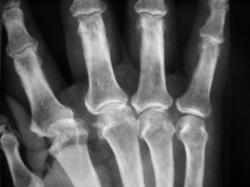

Катенёв Валенти... Дата публикации 03.07.2009, 23:53 Пациент направлен в рентгеновский кабинет "для рентгенографии кистей" терапевтом с диагнозом "Ревматоидный артрит". Произведены рентгенограммы. Ваше мнение коллеги? Сб, 04/07/2009 - 00:59 #1 Петрович Не на сайте Был на сайте: 7 лет 2 месяцев назад Зарегистрирован: 22.03.2009 - 01:13 Публикации: 3908 Для полноценной диагностики "Ревматоидного артрита" маловато представлено костей запястья. А из того, что представлено видна Подагра. Или нет? Неоднозначно всё Сб, 04/07/2009 - 12:12 #2 Ермолаев Не на сайте Был на сайте: 8 лет 10 месяцев назад Зарегистрирован: 07.02.2009 - 16:33 Публикации: 670 Соглашусь с мнением Петровича! Больше похоже на подагрический артрит. dok Вс, 05/07/2009 - 01:12 #3 OPEXOB Не на сайте Был на сайте: 9 лет 11 месяцев назад Зарегистрирован: 26.07.2008 - 10:02 Публикации: 280 Господа, мнения разделились. Поясните, кто что видит, а не окончательный диагноз. Подагра? где тофусы, "пробойники". Вс, 05/07/2009 - 12:31 #4 Ермолаев Не на сайте Был на сайте: 8 лет 10 месяцев назад Зарегистрирован: 07.02.2009 - 16:33 Публикации: 670 Коллега Орехов! Мнения, как раз и не разделились, а сошлись в одном - подагра. dok Вс, 05/07/2009 - 15:50 #5 alexey.krasnov Не на сайте Был на сайте: 10 лет 3 месяцев назад Зарегистрирован: 19.05.2009 - 10:52 Публикации: 30 Абсолютно согласен с Др. Ермолаевым и остальными. Bis Dat Qui Cito Dat

Для полноценной диагностики "Ревматоидного артрита" маловато представлено костей запястья. А из того, что представлено видна Подагра. Или нет?

Соглашусь с мнением Петровича! Больше похоже на подагрический артрит.

Коллега Орехов! Мнения, как раз и не разделились, а сошлись в одном - подагра.